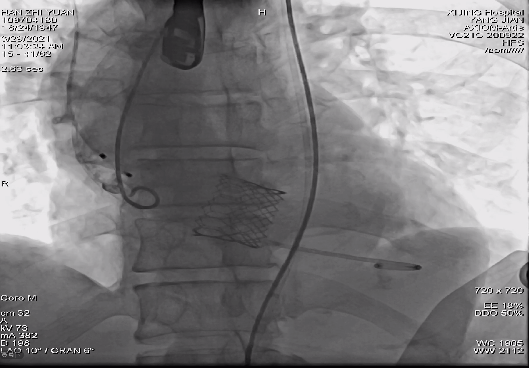

病例一

Prizvalve®瓣膜系统TAVR术后位置良好、造影无瓣漏